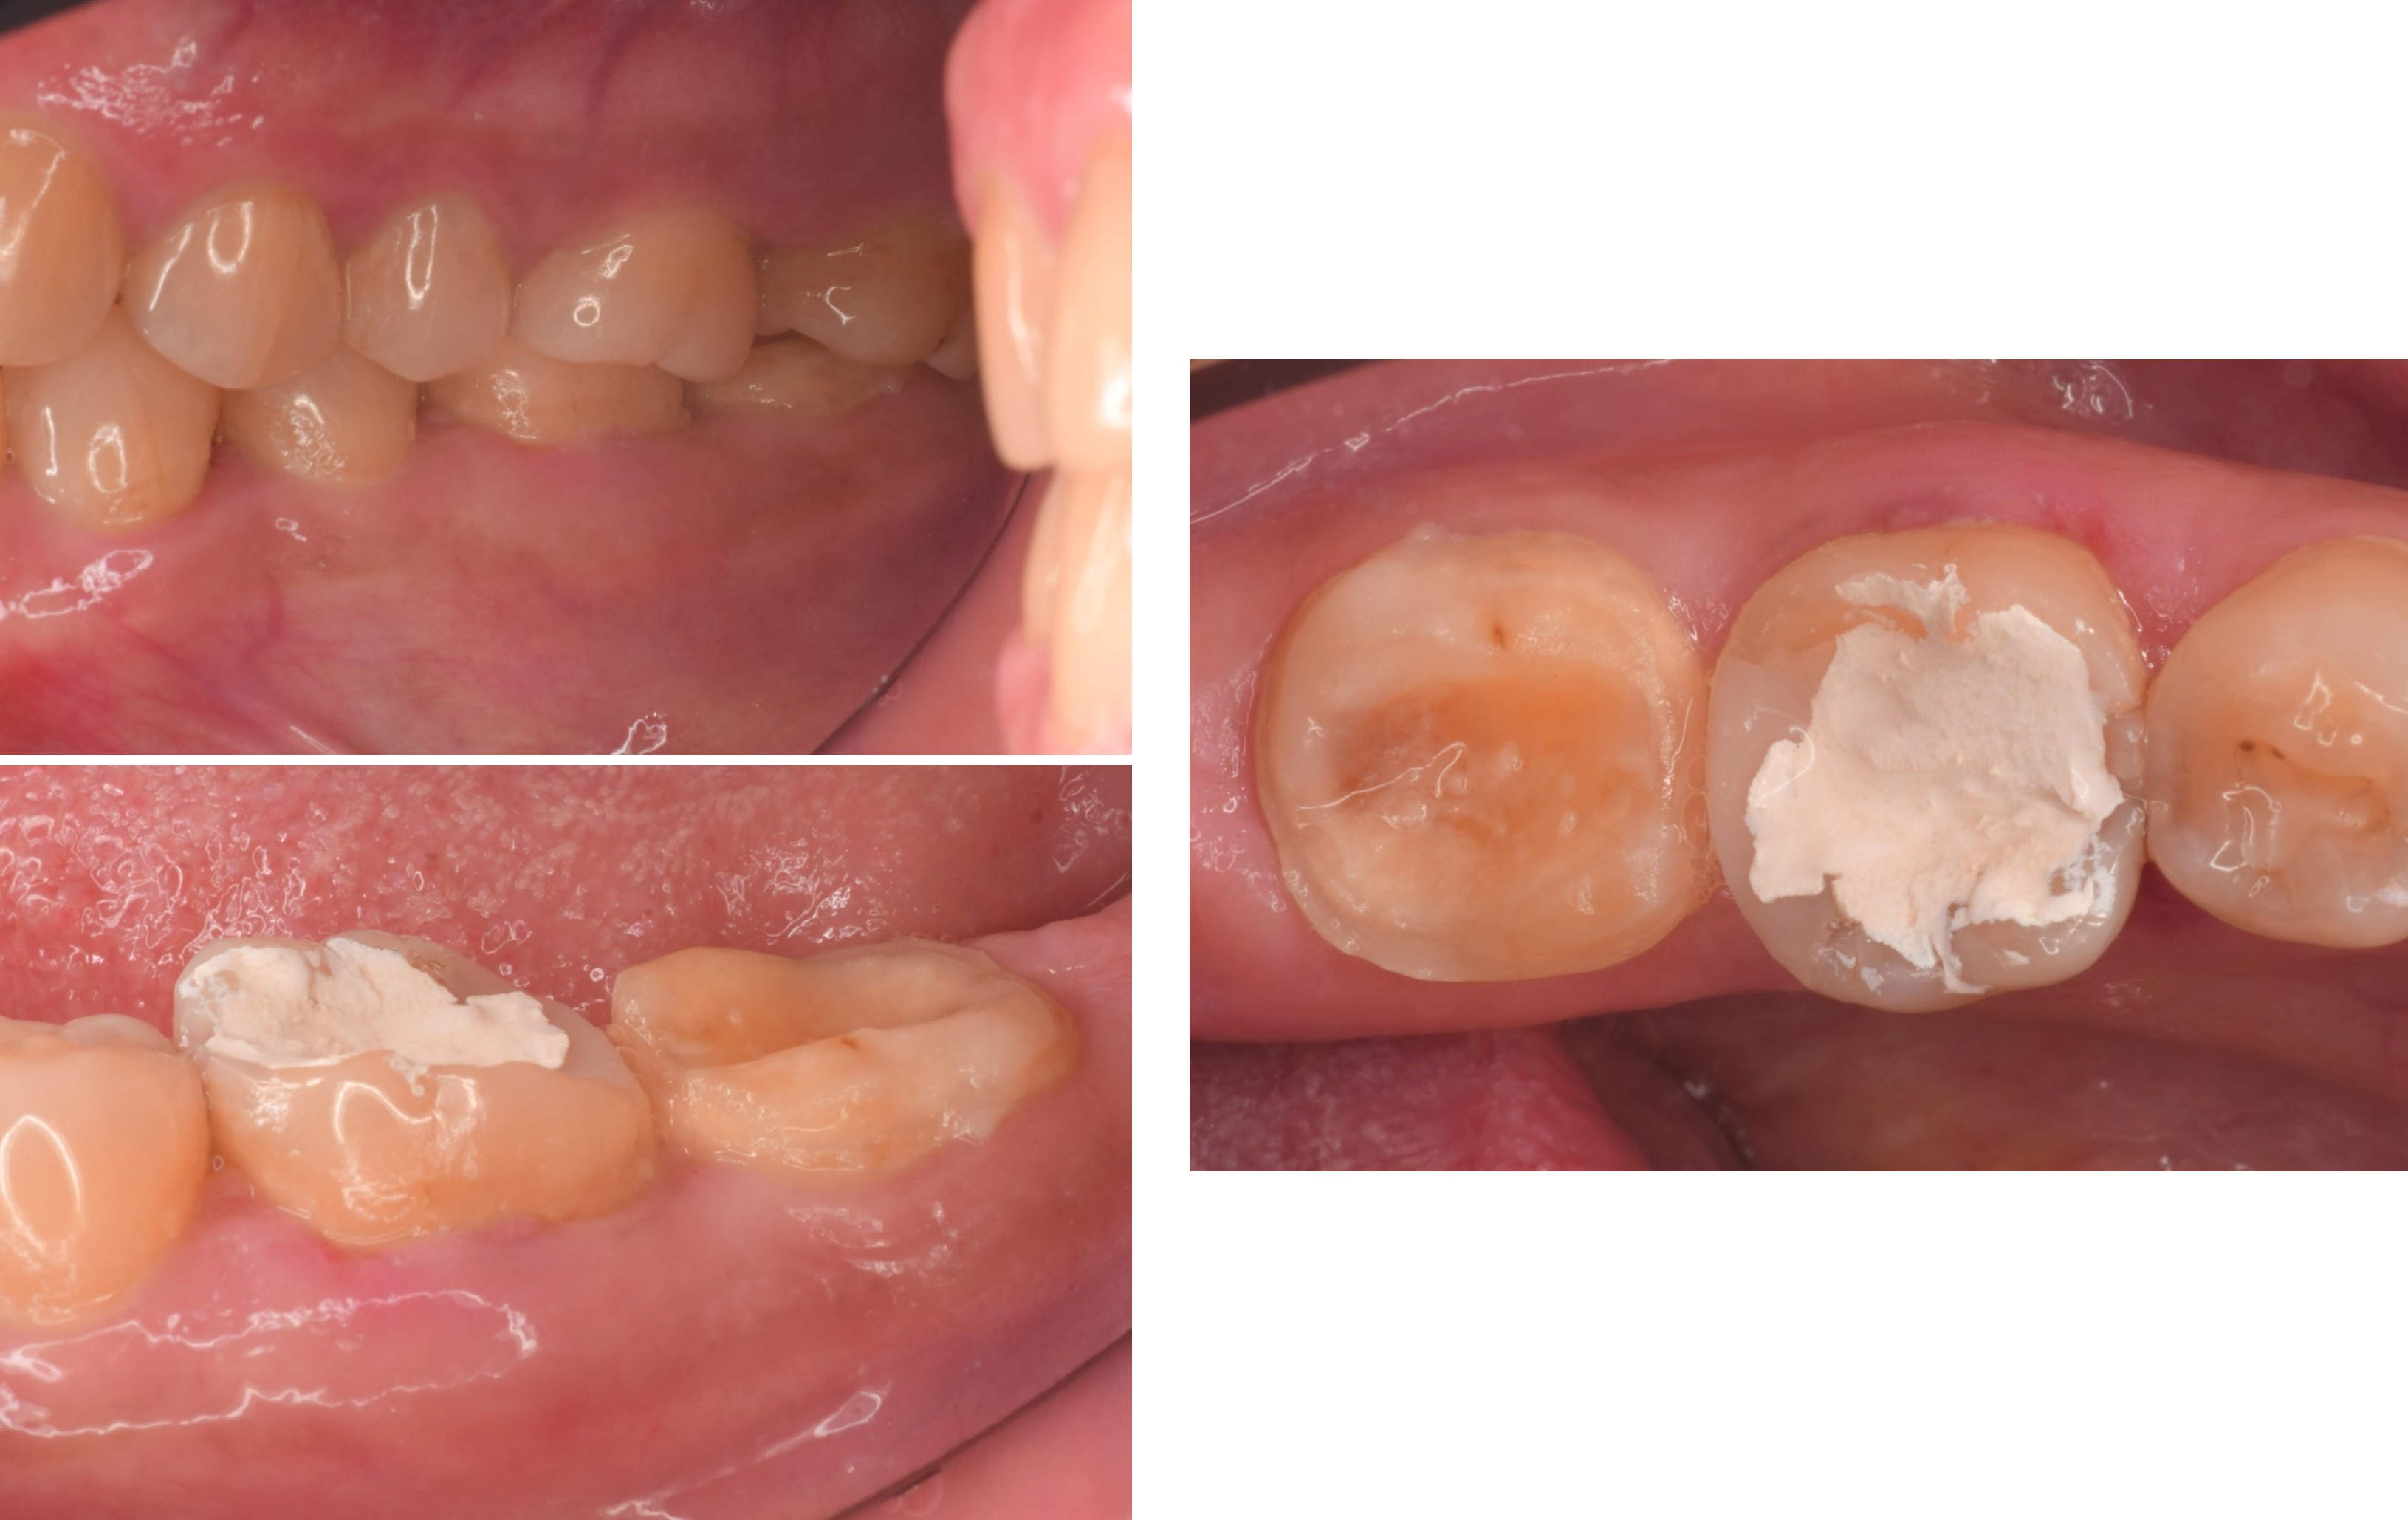

治療前,左下大臼齒區蛀牙